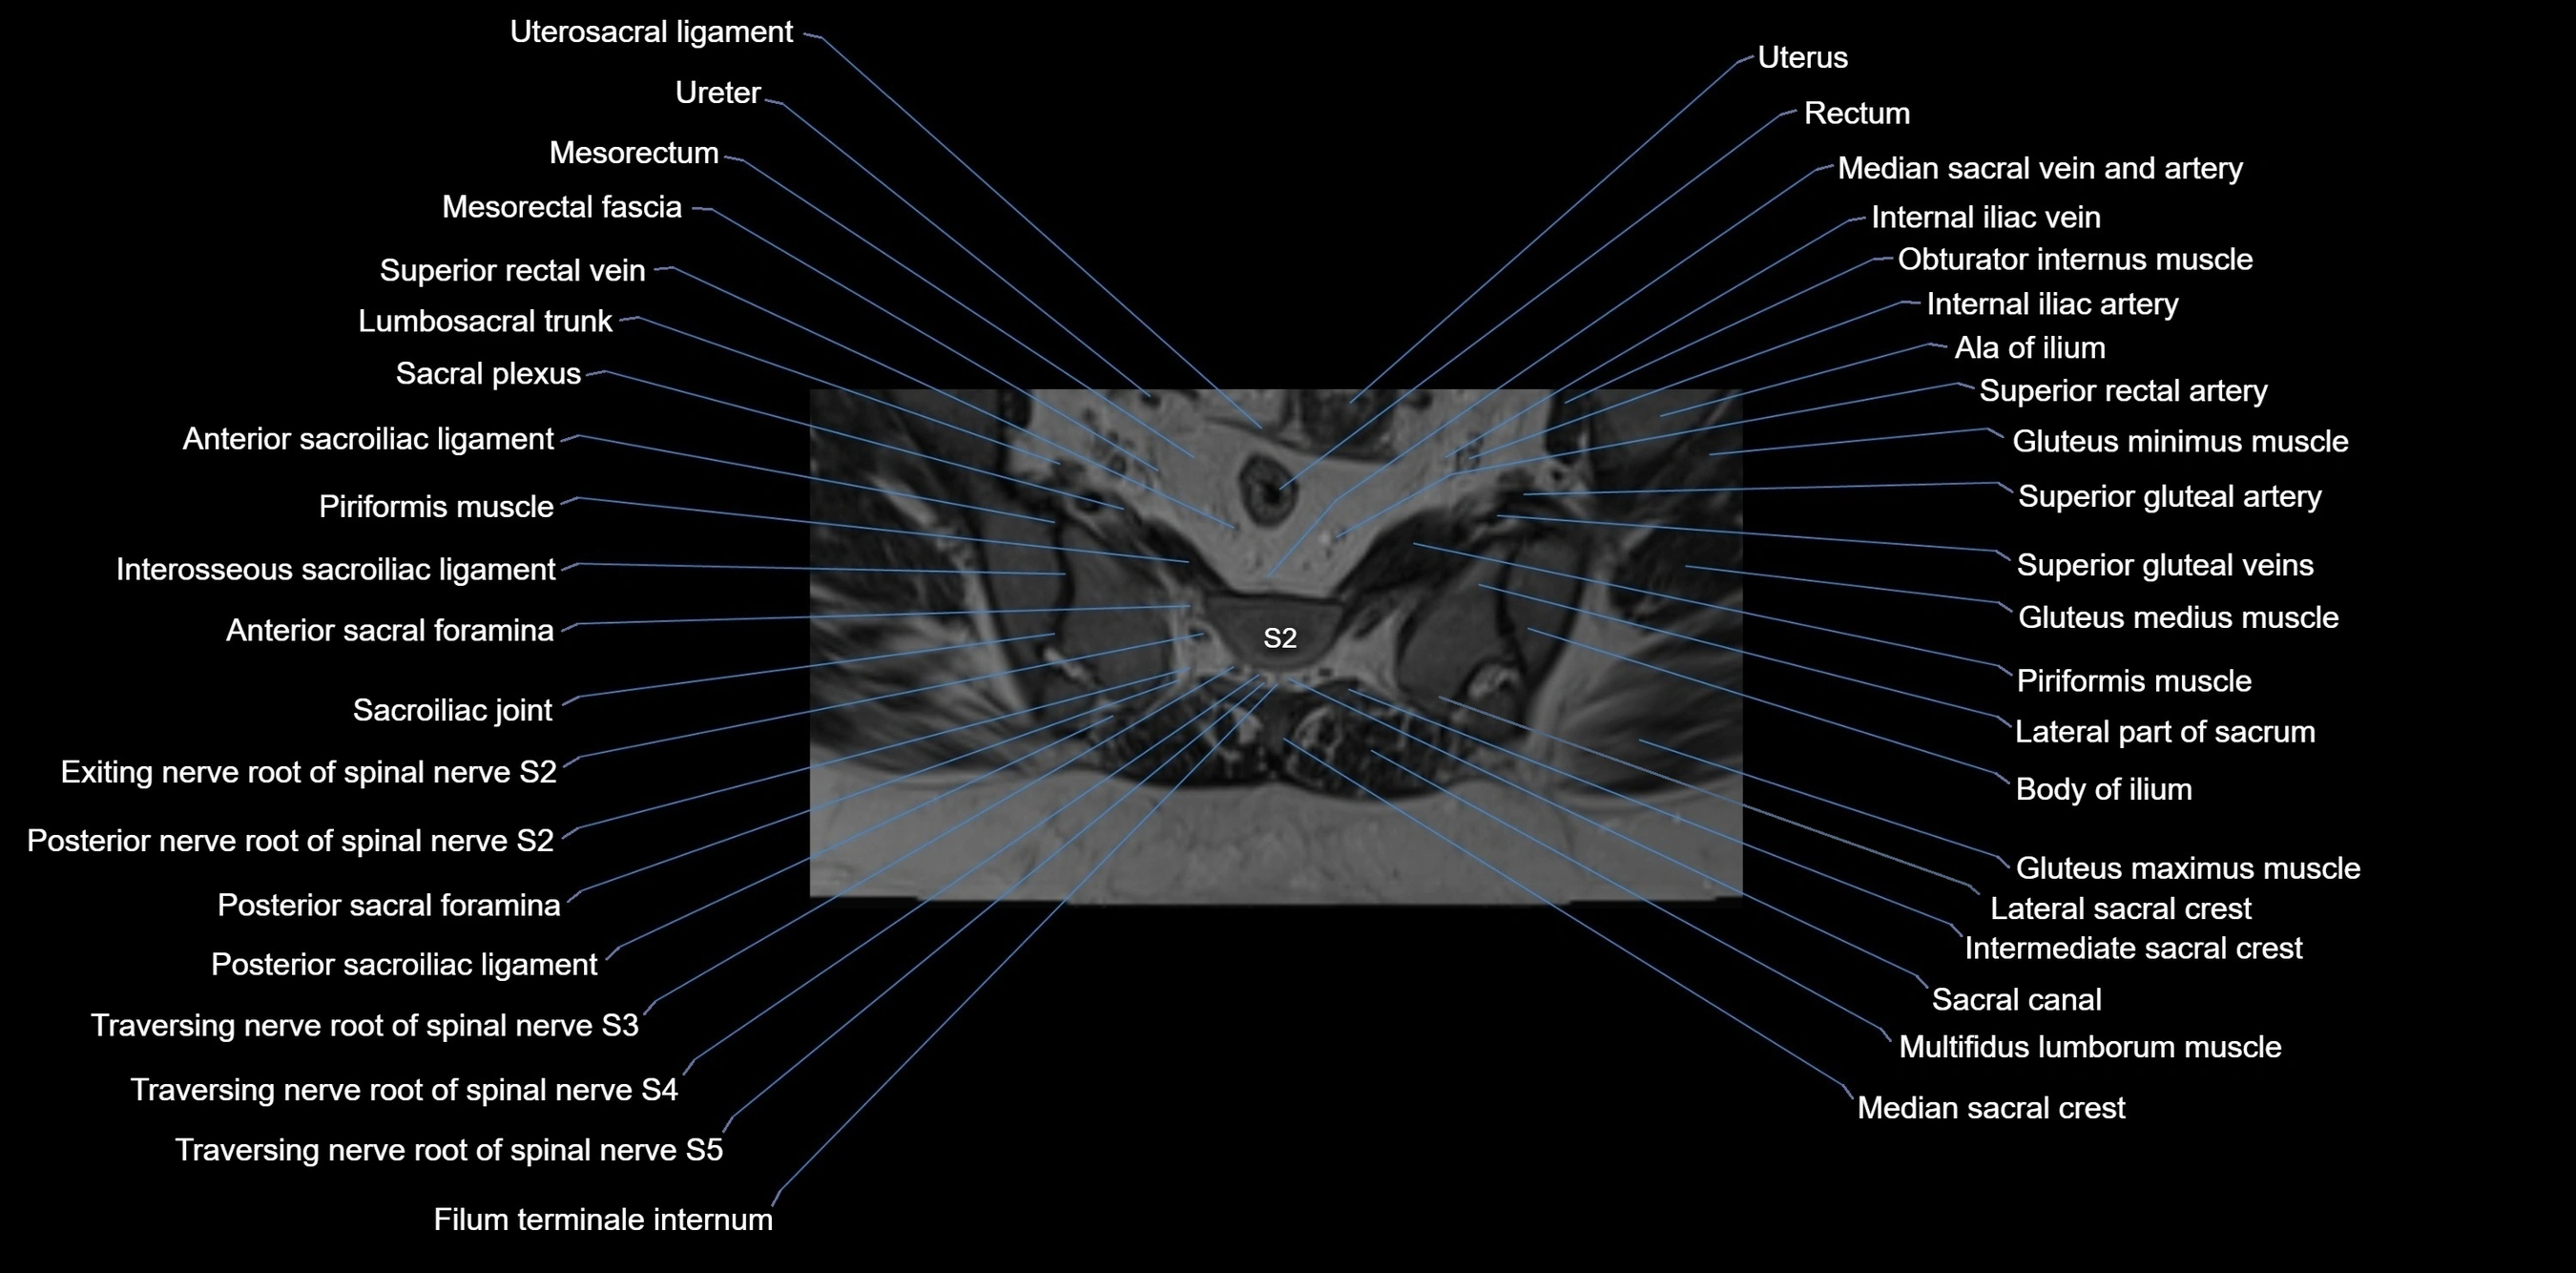

MRI image

image